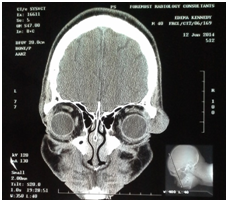

A 40 year old man presented with a 10 year history of painless progressive swelling of the lateral two-thirds of the right upper eyelid. There was no history of proptosis, reduction in vision, ocular deviation or diplopia. There was no history of similar swelling in the past involving either eyelid or history of swelling in other parts of the body. Systemic review was not significant. On examination, the best corrected visual acuity was 6/6 in both eyes. The main finding was a firm, non-tender, S-shaped mass on the lateral two-thirds of the right upper eyelid measuring 4×4×3cm. The swelling extended over the zygomatic bone; the overlying skin was normal as shown in Figure 1a&b. Other ocular and systemic examination was essentially normal. Orbital CT scan revealed a soft tissue mass (22x15x19mm) located on the right lateral aspect of the lacrimal gland bed. The mass showed punctate calcification. There was no evidence of erosion of the zygomatic bone or infiltration of the surrounding fat. The lateral rectus was normal. The left orbit was normal as demonstrated in Figure 2a&b. Excisional biopsy was done through a lid crease incision and a purplish mass measuring 2.5×1.5×1cm was found as depicted in Figure 3. Histopathological examination revealed an encapsulated mass with a homogenous dark cut surface on macroscopic examination. Microscopic examination of histologic sections showed a tumor composed of large dilated vascular channels filled with blood. The vascular channels are separated by connective tissue stroma. There was no atypia.

Figure 2a&b The left orbit was normal.